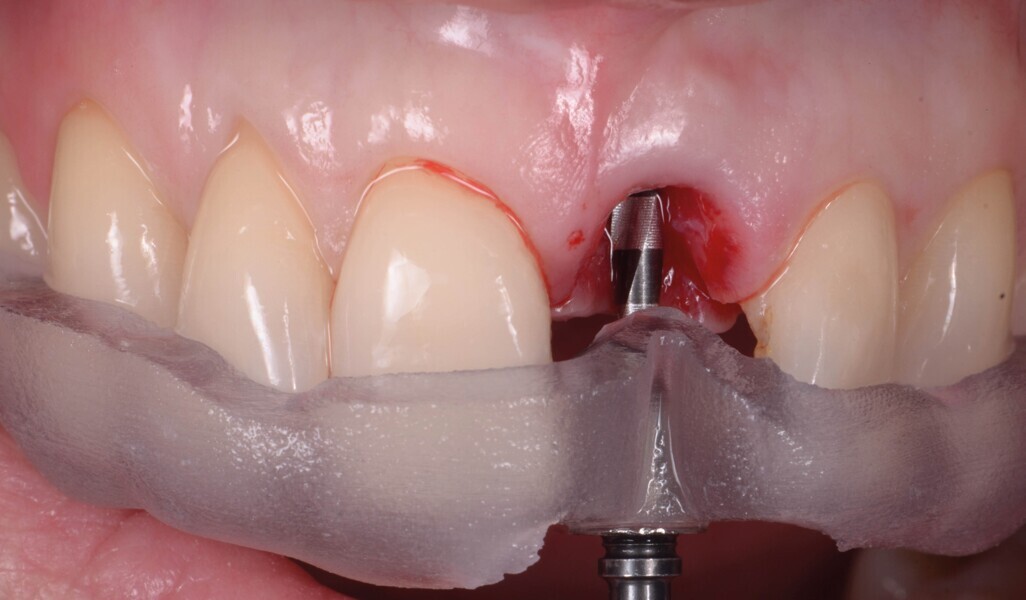

Fig. 10a: Un guide avec forage pilote est fabriqué d’après les reconstructions CBCT en 3D.

Fig. 10b : Un guide avec forage pilote est fabriqué d’après les reconstructions CBCT en 3D.

Fig. 10c : Un guide avec forage pilote est fabriqué d’après les reconstructions CBCT en 3D.

Fig. 11a : Position de forage optimisée du premier foret. La partie interne contient un manchon de forage en titane, pour assurer la précision de l’angulation et du niveau de butée (b).

Fig. 11b : Position de forage optimisée du premier foret. La partie interne contient un manchon de forage en titane (a), pour assurer la précision de l’angulation et du niveau de butée (b).

Fig. 12a : Un second guide fabriqué sur la base du wax-up diagnostique. La morphologie de la dent et le profil d’émergence ont été reproduits et servent de référence pour le positionnement de l’implant. (a et b).

Fig. 12b : Un second guide fabriqué sur la base du wax-up diagnostique. La morphologie de la dent et le profil d’émergence ont été reproduits et servent de référence pour le positionnement de l’implant. (a et b).

Aucune concavité vestibulaire n’est présente et le contour de crête est correct. À ce stade, l’objectif principal est atteint : la cicatrisation post-extractionnelle est atteinte. La priorité passe des lors a la préservation de l’architecture des tissus lors de la phase implantaire. À cet effet, un protocole combinant l’élévation d’un lambeau de petite étendue et une chirurgie guidée avec forage pilote est alors exécuté (Fig . 10).

Un implant (Aadva Regular, GC Tech), avec une connexion conique interne associée au concept du platform switching, est mis en place (Figs. 11–12). La dent provisoire est ensuite collée à nouveau aux dents adjacentes